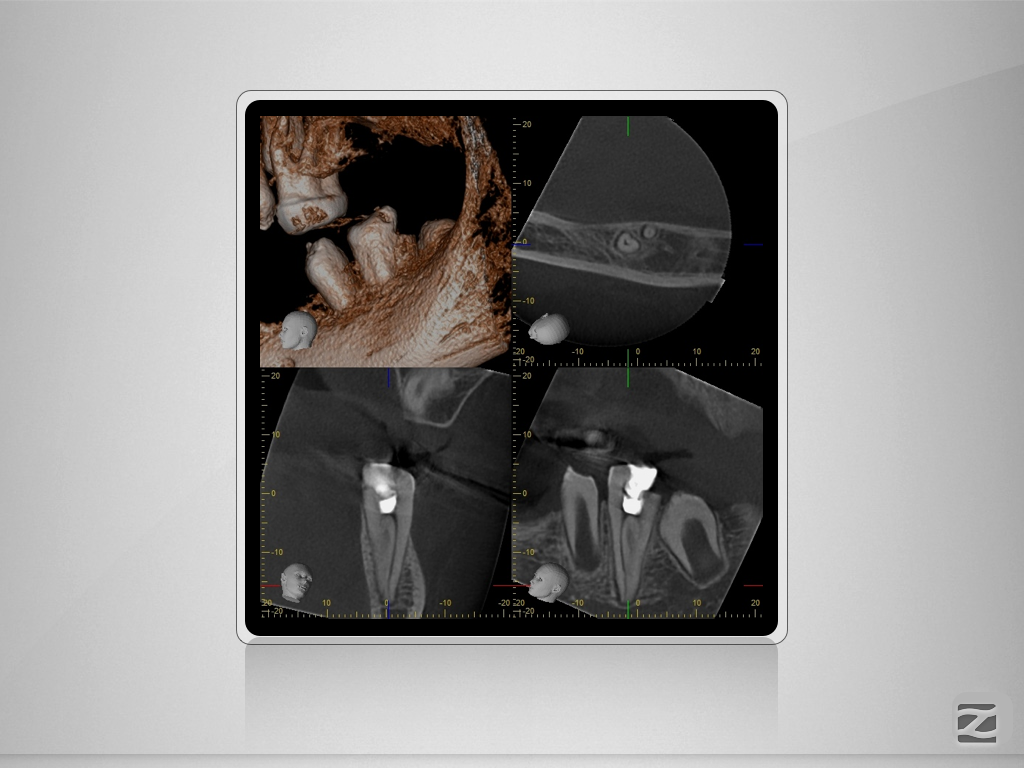

36D.006

Wie wäre es ohne DVT?